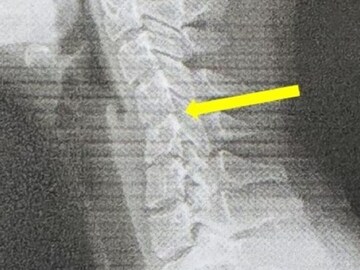

পরীক্ষার সময় এক্স-রেতে দেখা যায়, তাঁর সারভাইক্যাল স্পাইন (ঘাড়ের হাড়) স্বাভাবিক ভাঁজ হারিয়ে ফেলেছে। কিছু জায়গায় কশেরুকার (vertebrae) মধ্যে স্লিপ সরে গেছে। এই অবস্থা সাধারণত “টেক্সট নেক” (Text Neck) নামে পরিচিত, যা অকালেই সারভাইক্যাল ডিজেনারেশন (ঘাড়ের হাড়ের ক্ষয়) এর লক্ষণ হতে পারে।